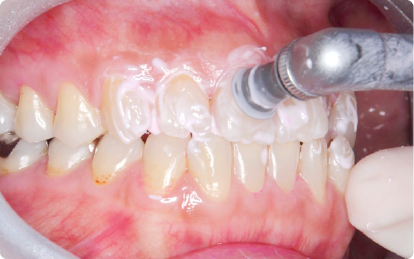

クリーニングでは、歯石やプラークを丁寧に除去し、歯と歯茎の健康を保ちます。また、正しい歯磨きやデンタルフロスの使い方など、口腔ケアの指導を行い、患者様自身が日常生活でできる予防法をお伝えします。

進行した歯周病は、スケーリング(歯石除去)やルートプレーニング(歯根の表面を滑らかにする処置)が必要です。